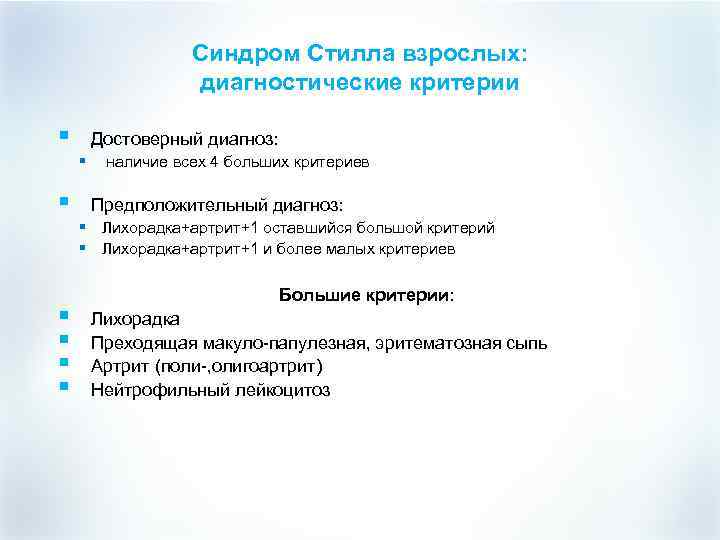

Синдром Стилла взрослых: диагностические критерии § Достоверный диагноз: § § наличие всех 4 больших критериев Предположительный диагноз: § Лихорадка+артрит+1 оставшийся большой критерий § Лихорадка+артрит+1 и более малых критериев § § Большие критерии: Лихорадка Преходящая макуло-папулезная, эритематозная сыпь Артрит (поли-, олигоартрит) Нейтрофильный лейкоцитоз

Синдром Стилла взрослых: диагностические критерии § Достоверный диагноз: § § наличие всех 4 больших критериев Предположительный диагноз: § Лихорадка+артрит+1 оставшийся большой критерий § Лихорадка+артрит+1 и более малых критериев § § Большие критерии: Лихорадка Преходящая макуло-папулезная, эритематозная сыпь Артрит (поли-, олигоартрит) Нейтрофильный лейкоцитоз